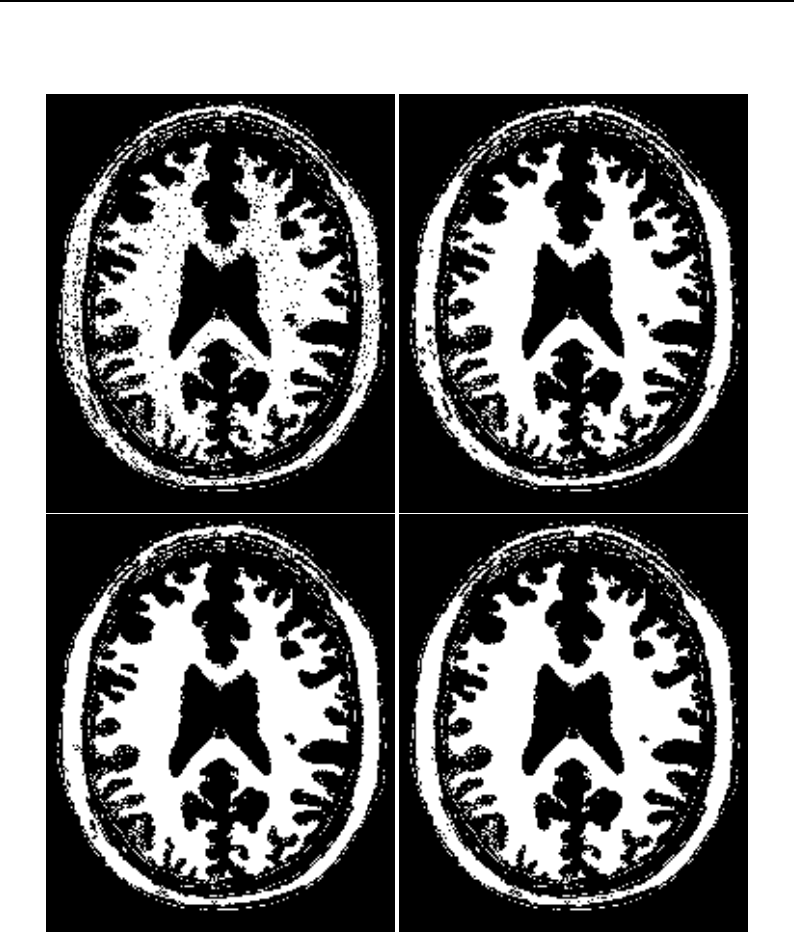

The National Library of Medicine Insight Segmentation and Registration Toolkit, shortened as the

Insight Toolkit (ITK), is an open-source software toolkit for performing registration and segmenta-

tion. Segmentation is the process of identifying and classifying data found in a digitally sampled

representation. Typically the sampled representation is an image acquired from such medical instru-

mentation as CT or MRI scanners. Registration is the task of aligning or developing correspondences

between data. For example, in the medical environment, a CT scan may be aligned with a MRI scan

in order to combine the information contained in both.